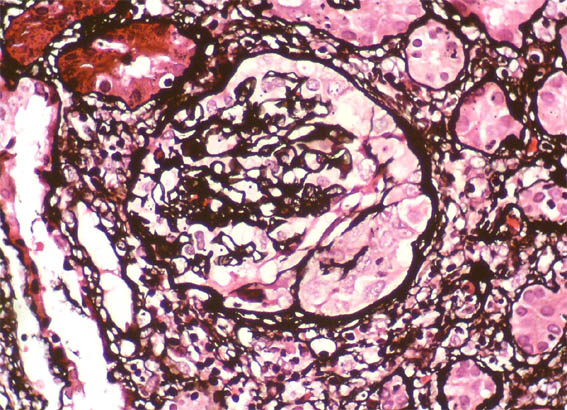

Figure 8. Methenamine-silver stain, X400.

What is the cause of the crescent evidenced in a glomerulus?